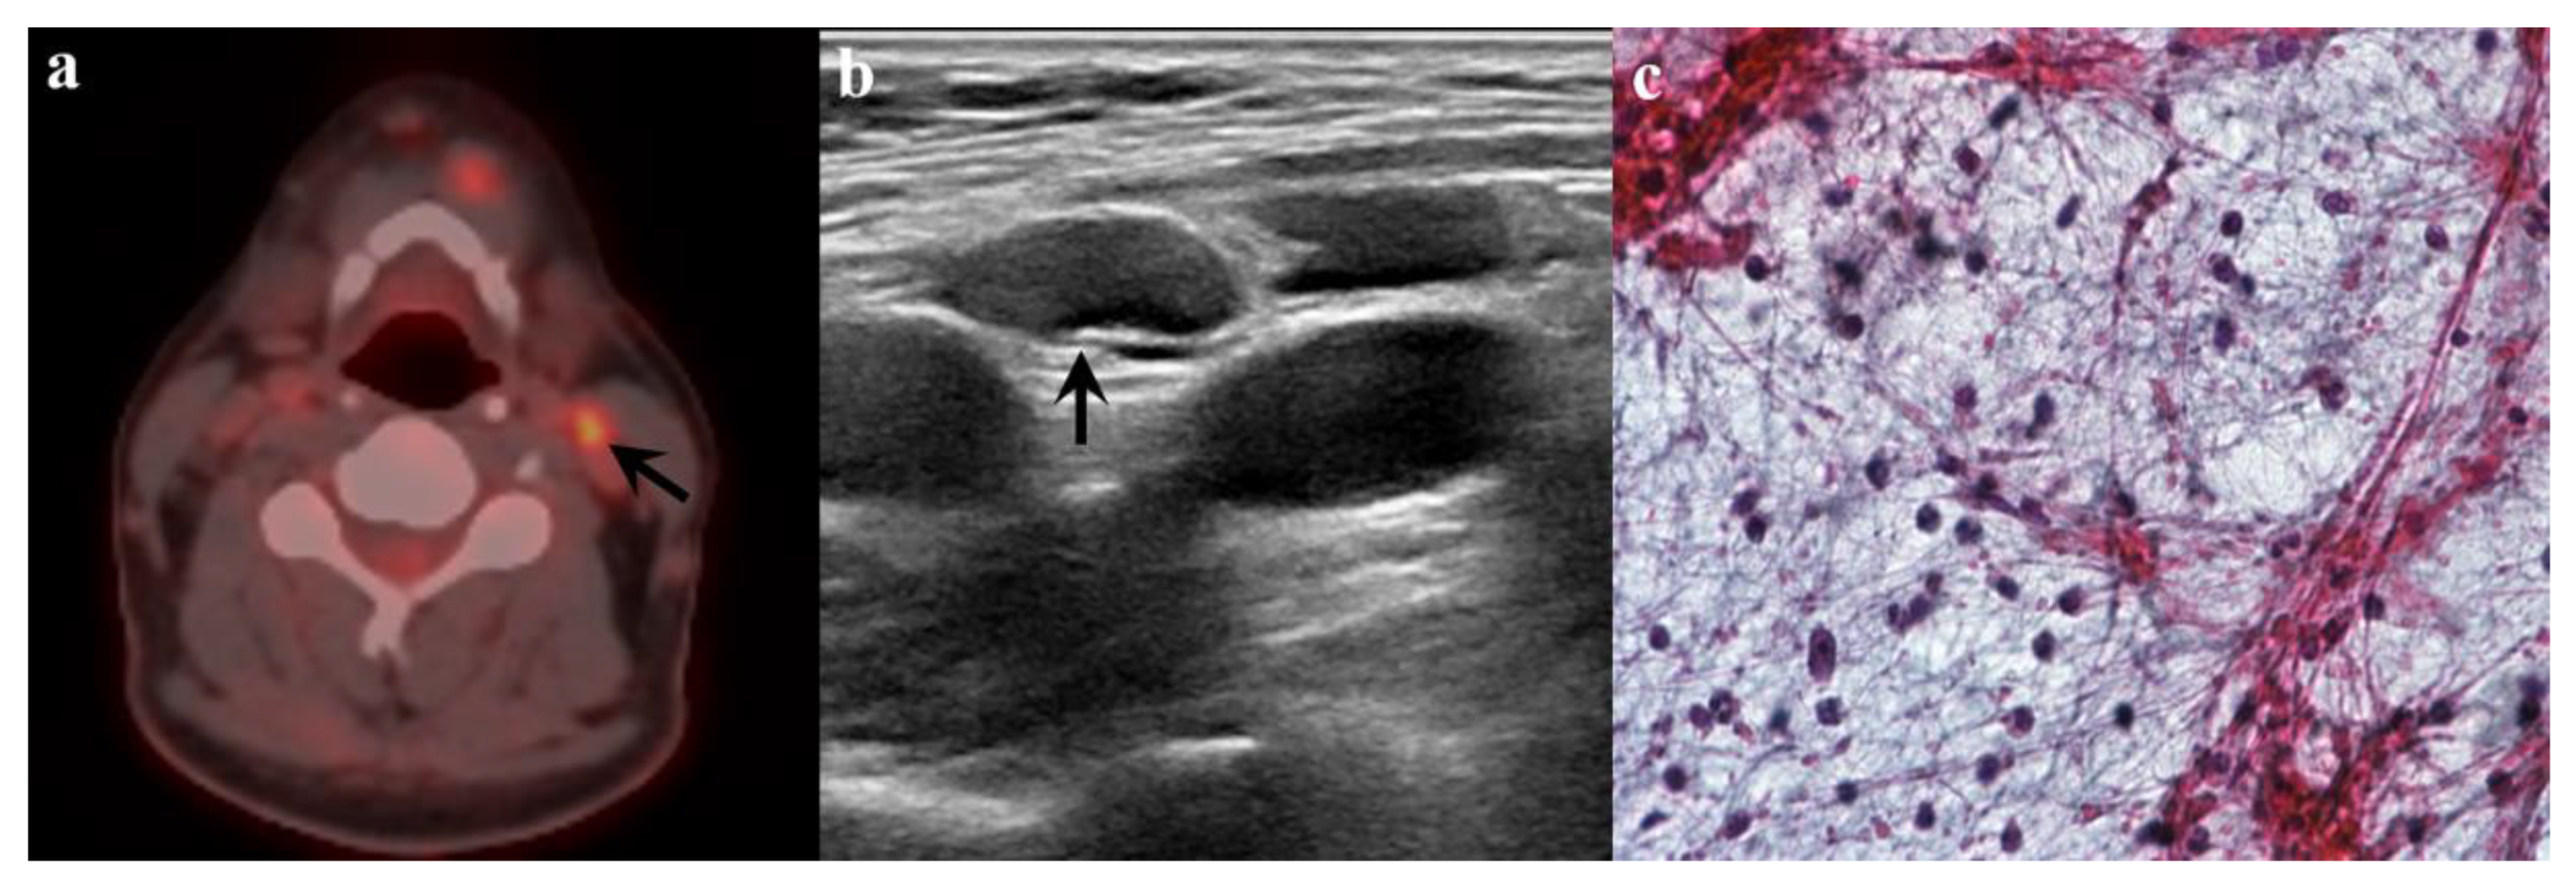

3.3. Subsequent US Findings

3.4. Combined Diagnosis Using Subsequent US Findings